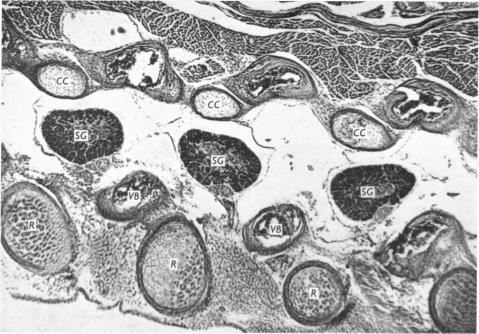

Reduced articular processes of thoracic vertebrae, a 'minor skeletal variant' in the mouse.

J Anat. 1968 Jan;102(Pt 2):311-20.